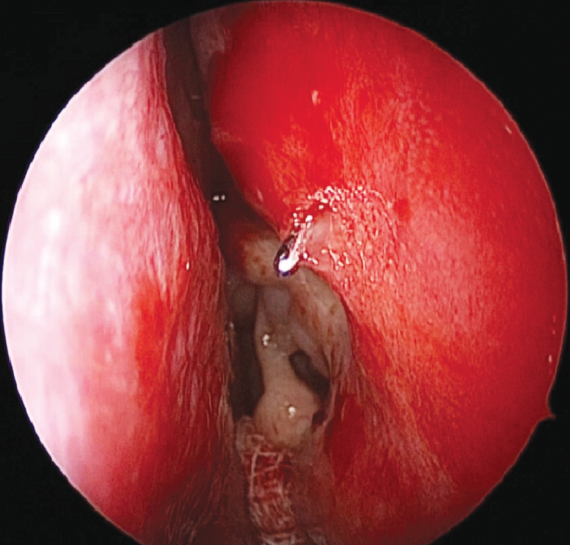

The intervention was performed as follows. Under local and conduction anesthesia with intravenous sedation, antegrade probing of the dacryostomy area was performed with the formation of an opening in the scar tissue (in three cases) and with probing of residual dacryostomy (in three cases; Fig. 2). Purulent discharge was removed from the lacrimal sac cavity using an aspirator. A balloon was inserted endonasally into the dacryostomy opening using a curved von Eicken cannula for irrigation with an outer diameter of 4.0 mm and length of 15 cm (Karl Storz, Germany; Fig. 3). Balloon dacryoplasty was performed according to the protocol we developed earlier in the experiment [8] and tested in the clinical setting (Fig. 4) [9]. The balloon was dilated at a pressure of 8 atm. for 90 s, and after 10 s, it was repeated for 60 s. After deflation, the balloon was removed. Figure 5 shows an enlarged dacryostomy after the intervention. A hemostatic sponge was inserted into the dacryostomy area, which was removed 48 h after the surgery.

Fig. 4. Endoscopic view of a left nasal cavity with an inserted and inflated balloon catheter

Рис. 4. Эндоскопическая картина полости носа (левая половина носа) с введённым и раздутым баллонным катетером

Fig. 5. Endoscopic view of dilated dacryostoma (left nasal cavity) following balloon dacryoplasty. The ostium was probed with Bowman probe

Рис. 5. Эндоскопическая картина области расширенной дакриостомы после баллонной дакриопластики (левая половина носа). Зонд Боумена выведён через дакриостому